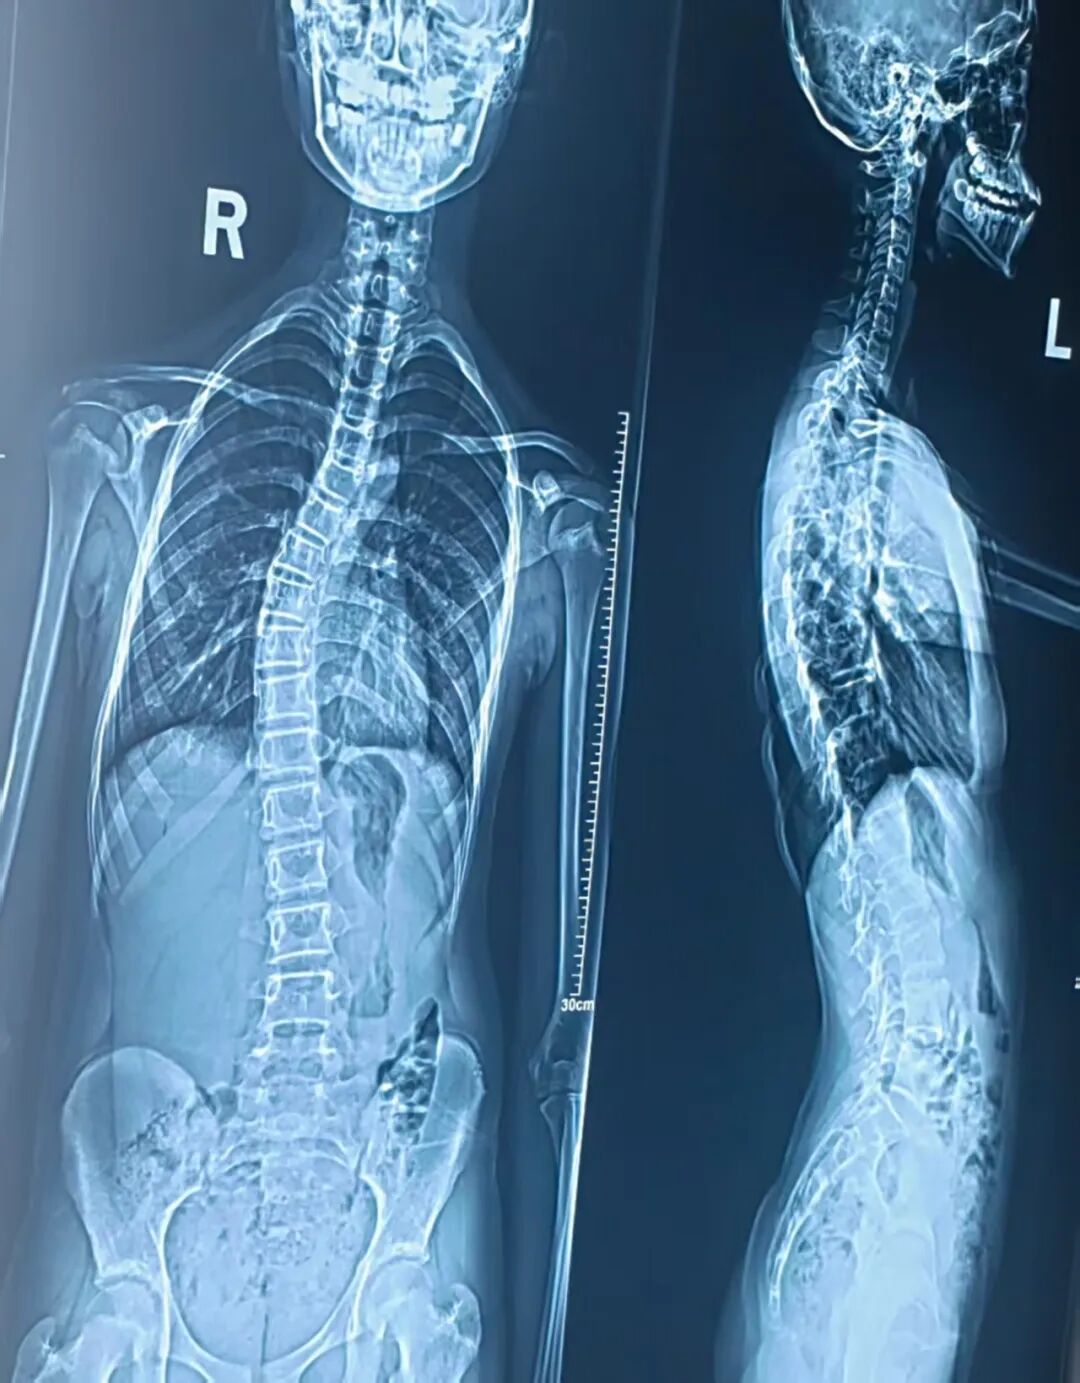

影像学检查是脊柱侧弯筛查与诊断的重要手段,其中 X 线摄片是 “金标准”(需注意其 X 射线辐射)。医生会通过 X 片测量 Cobb 角,判断侧弯严重程度,并制定针对性方案。

从X片上看,当脊柱偏离躯干正中线时,在脊柱头侧端椎上缘的垂线与尾侧端椎下缘的垂线之间会形成一个交角,医学上称为cobb角。